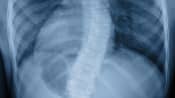

Posterior view of the adolescent spine showing thoracic scoliosis.

X-ray scan showing spine curvature caused by scoliosis